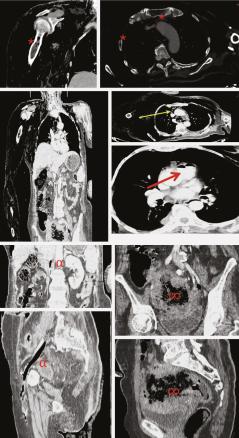

Une femme de 70 ans, diabétique, suivie pour un cancer du côlon depuis un an et demi, sous chimiothérapie, se plaint, depuis la veille de son admission aux urgences, de douleurs intenses au niveau du membre supérieur droit avec apparition de phlyctènes (fig. 1 ) ainsi qu’au niveau des jambes (fig. 2 ) et du torse. Cliniquement, la patiente est confuse, hypotendue, avec à la palpation des crépitations au niveau cervico-thoracique et au niveau du membre supérieur droit. Le bilan infectieux est positif, avec des globules blancs à 20 000/mm3 et une protéine C-réactive (CRP) à 432 mg/L. Un scanner cervico-thoraco-abdomino-pelvien et des membres avec injection est réalisé. Il montre un important emphysème disséquant des parties molles cutanées, sous-cutanées et musculaires des parois cervico-thoraco-abdominales ainsi que des deux membres supérieurs et du membre inférieur gauche, associé à un pneumomédiastin de moyenne abondance, une aéroportie, quelques bulles d’air au niveau du tronc des artères pulmonaires, de la veine cave inférieure, des veines iliaques commune et externe gauches et des veines fémorales homolatérales et en intra-osseux au niveau sternal, de la clavicule, de l’omoplate, des quatre premières côtes et de l’humérus droits (fig. 3 ). Le scanner montre également une embolie pulmonaire segmentaire lobaire moyenne et une occlusion totale de l’artère axillaire droite, sans reprise d’aval, ainsi que le processus tumoral sigmoïdien localement avancé déjà connu. Après parage des lésions du membre supérieur droit et inférieur gauche, la patiente est hospitalisée en unité de soins intensifs. L’hémoculture révèle la présence de Clostridium septicum. La patiente décède malheureusement seize heures après son admission.